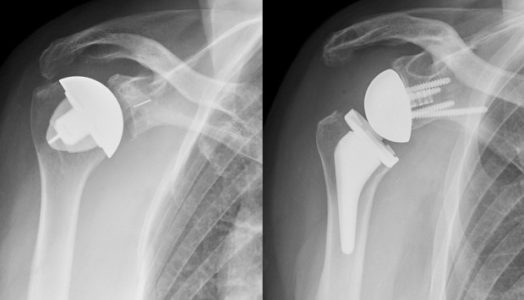

Ολική αρθροπλαστική ώμου (ορθόδρομη και ανάστροφη)

Ο ώμος είναι μια από τις μεγαλύτερες αρθρώσεις στο σώμα, ουσιαστικής σημασίας για τη λειτουργία του άνω άκρου, αλλά και ολόκληρου του σώματος. Μοιραία μπορεί να προσβληθεί από οστεοαρθρίτιδα, τη «νόσο της φθοράς» των αρθρώσεων, αλλά και από άλλες παθολογικές καταστάσεις, όπως οι ρευματοπάθειες ή οι χρόνιες τενοντοπάθειες. Δεν είναι λίγες ακόμη οι περιπτώσεις που η άρθρωση του ώμου μπορεί να υποστεί καταστροφική βλάβη μετά από κάποιο κάταγμα, γεγονός αρκετά συχνό σε ηλικιωμένους ασθενείς με συνυπάρχουσα οστεοπόρωση.

Μέχρι πρόσφατα ασθενείς με τέτοιες βλάβες ήταν αναγκασμένοι να υποστούν τις οδυνηρές συνέπειες της χρονιάς πάθησης ή του τραυματισμού τους. Ωστόσο, η ολική αρθροπλαστική του ώμου (ορθόδρομη και ανάστροφη) έχει πλέον καθιερωθεί ως μέθοδος θεραπείας με εντυπωσιακά αποτελέσματα. Σε αυτή την εγχείρηση αντικαθίστανται οι αρθρούμενες επιφάνειες των οστών του ώμου (κεφαλή βραχιονίου και ωμογλήνη ωμοπλάτης), ώστε να επανέλθει η λειτουργία του σχεδόν στο φυσιολογικό. Είναι μάλιστα μια εγχείρηση που έχει τεράστια αύξηση στον αριθμό ασθενών που υποβάλλονται σε αυτήν, κυρίως ασθενών  με κατάγματα του ώμου, οι οποίοι σε άλλη περίπτωση θα έπρεπε απλώς να αφεθούν στην τύχη τους.